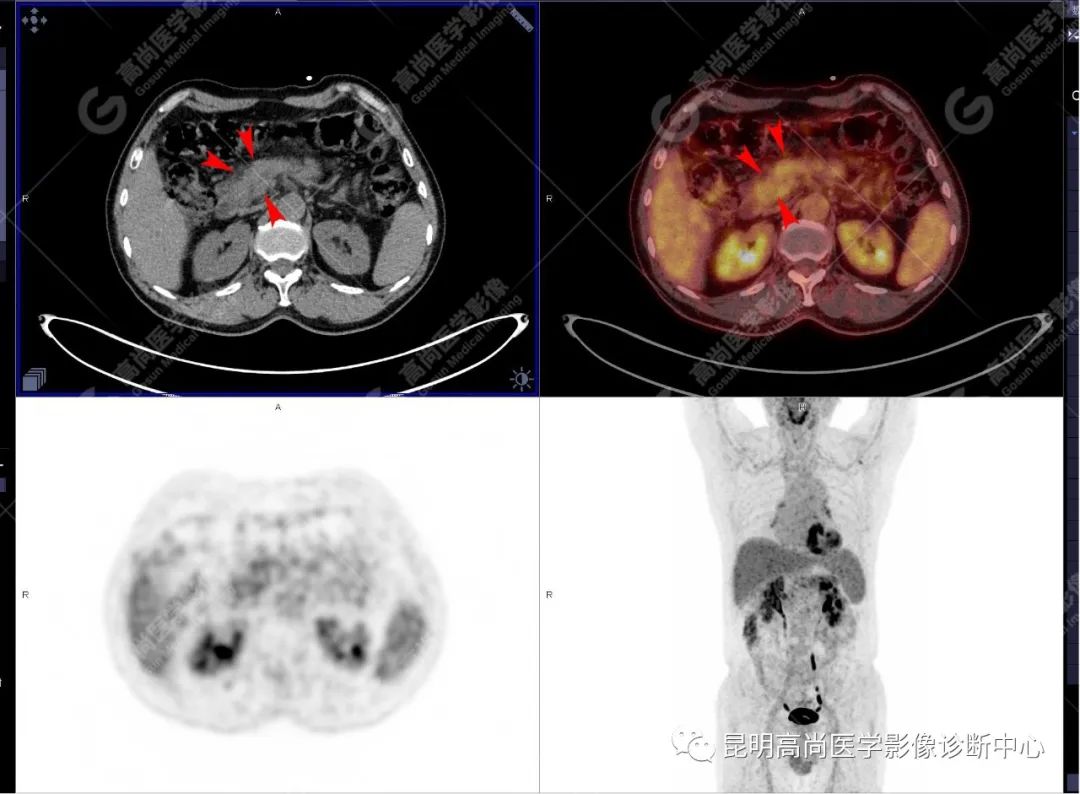

十二指肠壶腹区等密度结节影伴糖代谢持续增高,多考虑恶性病变(壶腹癌),继发主胰管扩张及慢性胰腺炎表现;腹膜后多发淋巴结显示,糖代谢不同程度增高,不除外转移。

(4)18F-FDG PET/CT

在诊断胰腺癌方面具有较高的敏感性,其敏感性可达 85%~90%,特异性可达 55.6%~94%;尤其在鉴别良恶性的囊性肿瘤时,其准确率可达到 94%~95%;PET/CT 是胰腺癌的主要检查手段,它比常规 CT 和 MRI 更具优势,可早期发现远处转移灶;同时可以作为一个独立的、用于预测胰腺癌生存和无进展生存的独立的指标,即 SUV,代谢肿瘤体积,即 MTV。